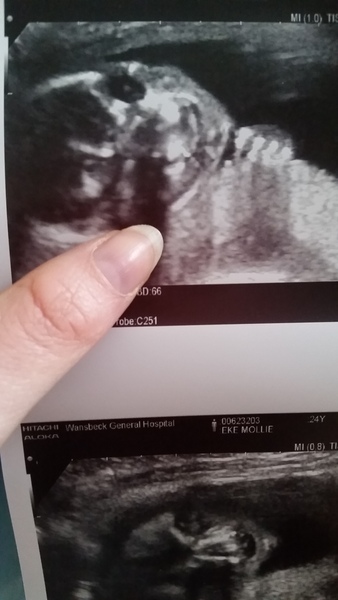

Everything went brilliantly, all measurements were fine and baby is healthy (though for awkward for the poor lady scanning me!)

No hope of accidentally seeing if we have pink or blue because little bean had their legs folded and was facing my spine using my placenta as a pillow!

Got a good shot of baby looking at the camera though Grin

Just realised I have massively outed myself 😂 never mind! Yeah I was glad as she didn't ask us wether we wanted to know or not! She said 'we've got a fe...mur' and paused a little too long after the 'fe' I thought she was going to say female! I could have cried haha! Team vanilla is staying strong Wink

Miley- yay congrats on healthy baby! Cool face picture!! Excited/scared for Monday!

Glad the scan went well Miley and that you stayed Team Vanilla!

Congratulations, Miley - lovely scan!

Beautiful scan Miley!

Miley lovely scan pictures!

miley lovely pic.